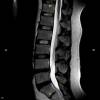

En nuestros centros se realizan estudios y diagnósticos de resonancia magnética musculo-esquelética

de Resonancia ,Magnética Musculo-Esquelética, de la marca italiana Esaote, es único en su diseño ya que nos permite realizar exámenes en bipedestación (el paciente estará de pie, para que se tenga otra perspectiva del comportamiento del cuerpo durante el examen).